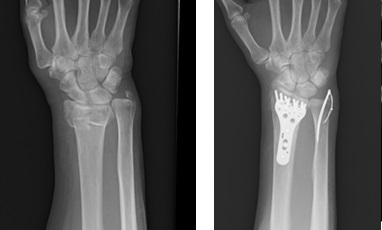

キーンベック病

誘因無く手関節が痛く力が入りにくくなる。XPで月状骨が破壊されてくる病気です。原因はわかりませんが、老人以外は進行してくることが多く積極的な治療が必要です。

治療方法

XP,MRIで病期を決定します。早期で橈骨が尺骨に比べて長い場合は橈骨短縮骨切り術、そうでない場合は当科では血管柄付き骨移植術を行っています。治療成績は非常に良好です。